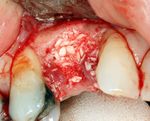

If bone width is inadequate it can be regrown using either artificial or cadevaric bone pieces to act as a scaffold for natural bone to grow around.